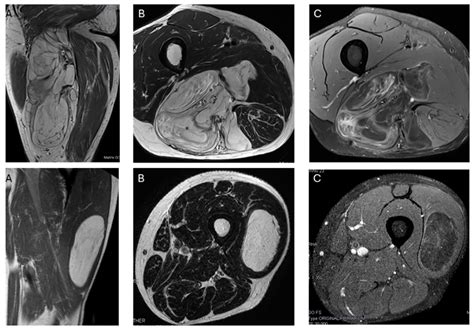

In contrast, a liposarcoma is a malignant (cancerous) tumor that arises from fat cells. Unlike lipomas, liposarcomas are rare. They belong to a category of cancers known as soft tissue sarcomas. While lipomas occur near the surface, liposarcomas often develop deep within the soft tissues of the body, such as deep in the thigh, the retroperitoneum (the area behind the abdominal cavity), or the limbs.

• MRI (Magnetic Resonance Imaging): This is the gold standard for evaluating soft tissue masses. It provides detailed images that help radiologists distinguish between simple fat tissue and more complex, suspicious-looking tumors.

• liposarcoma vs lipoma mri